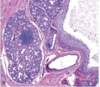

schneiderian papilloma

schneiderian papilloma, endophytic type